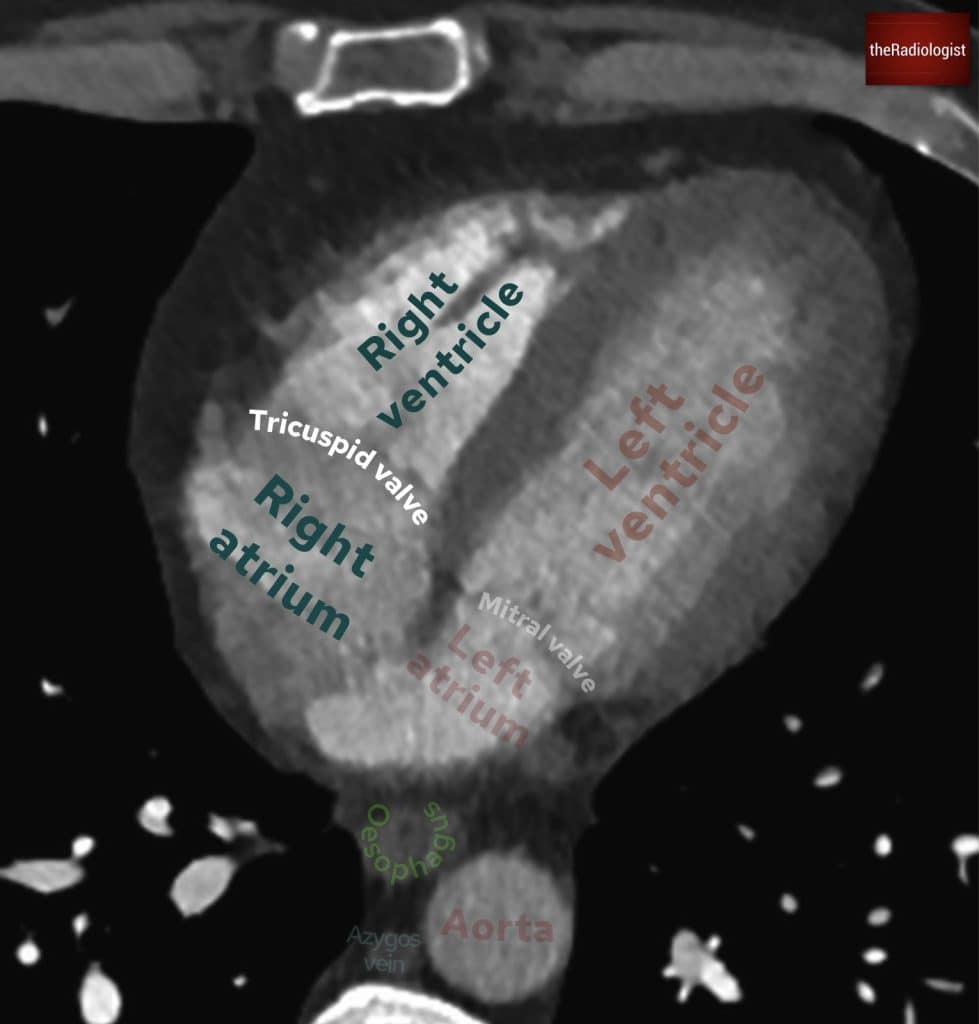

Follow the contrast from the subclavian vein into the brachiocephalic vein on either the left or the right. This will then feed into the superior vena cava and into the right atrium. On a CTPA study, this should appear bright. The contrast will then pass through the tricuspid valve into the right ventricle.

Follow the brachiocephalic veins into SVC and then down into the right atrium. From here you can follow the contrast through the tricuspid valve into the right ventricle.

Now, follow the contrast all the way out into the pulmonary arteries and then back into the pulmonary veins, which lead into the left atrium, through the mitral valve into the left ventricle, and then up into the aorta.

Annotated view of a CT chest showing the pulmonary veins draining into the left atrium.